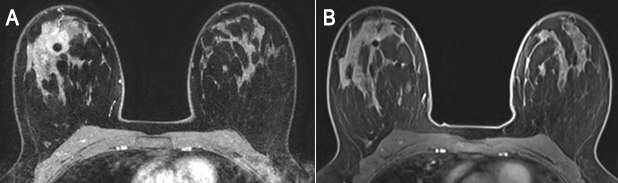

Figure 4. 52-year-old female with left breast tenderness was referred for breast MRI to assess for implant rupture. Axial STIR image shows bilateral silicone breast implants with the linguini sign seen in the left implant, suggestive of intracapsular rupture.